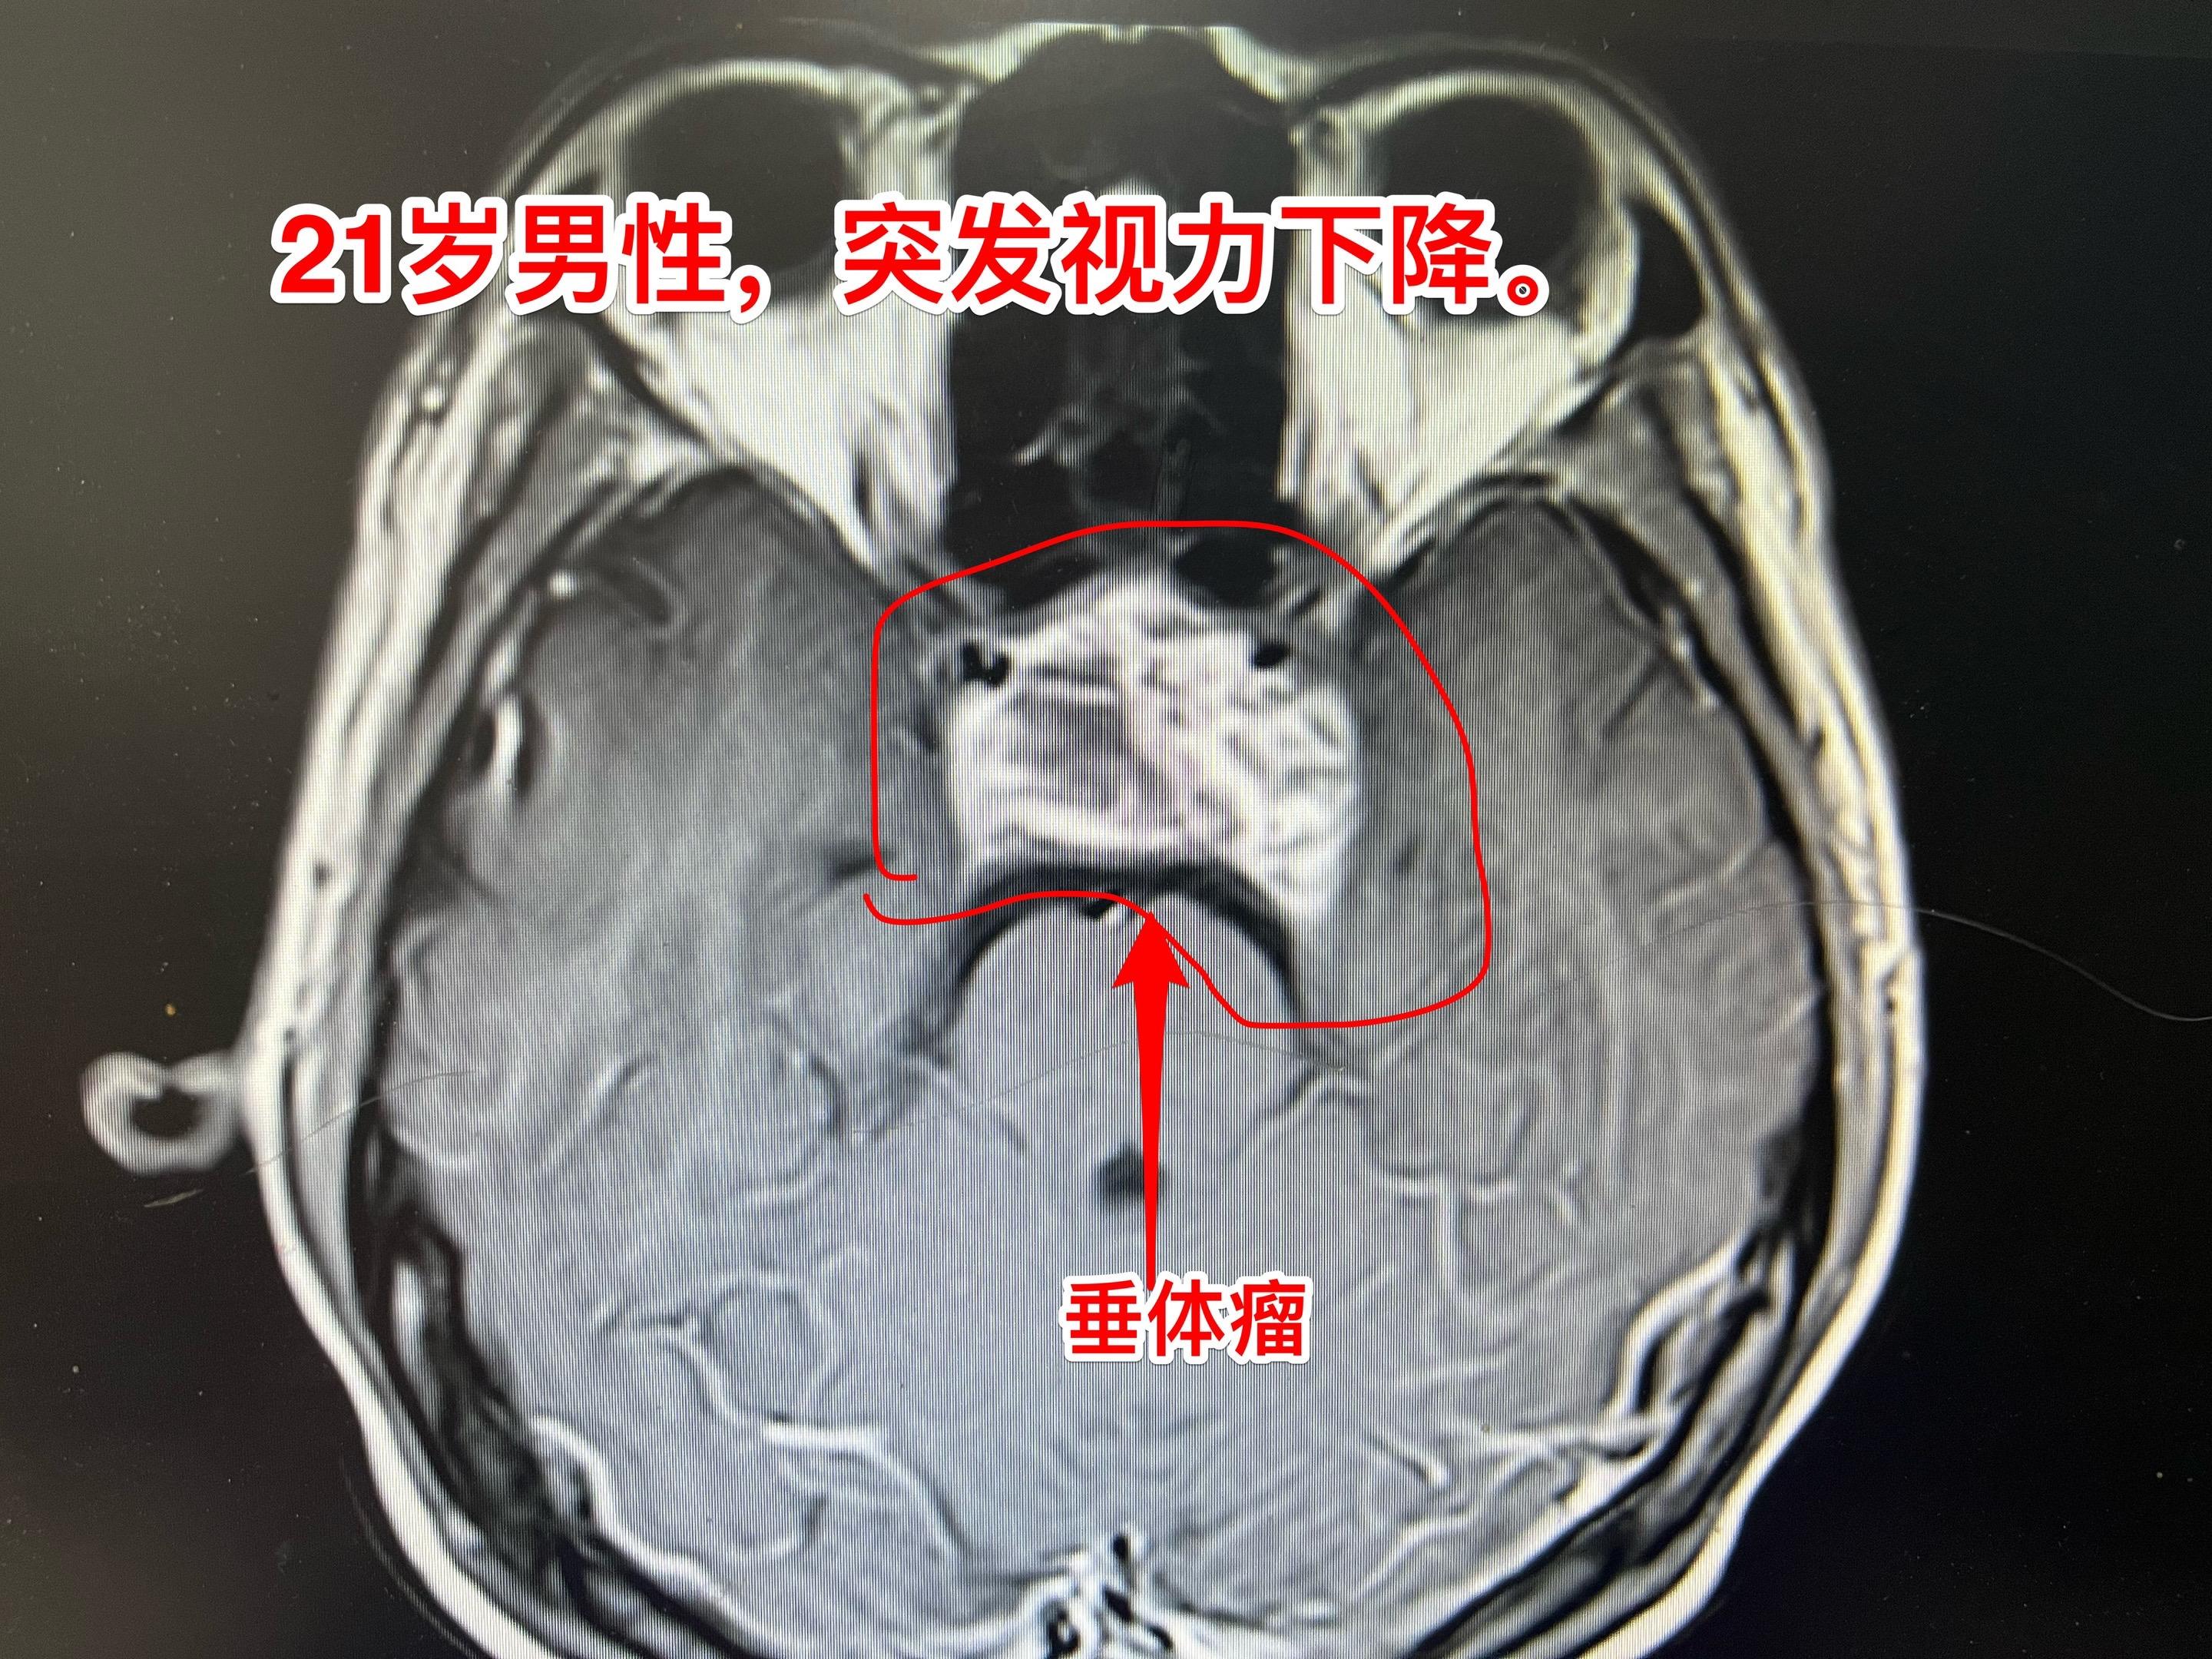

两个月内两个垂体瘤卒中 病例 垂体瘤卒中的最明显的症状是突发视力下降,可以伴有头痛。病人到医院眼科就诊一般找不出眼科的疾病,这时候只要作一个头部CT或者磁共振即可确诊垂体瘤卒中。一旦确诊,则应该尽快行手术切除垂体瘤,对视神经进行减压,争取挽救视力。 图1-6:男性,21岁,入院前六天突发视力下降,几乎双眼失明。在当地医院曾经怀疑是颅咽管瘤。在我科住院后给予激素治疗、对症治疗后视力呈现好转趋势。化验结果显示垂体功能低下(甲状腺激素低下、肾上腺皮质功能低下、性激素低下)。7月3日经鼻手术切除垂体